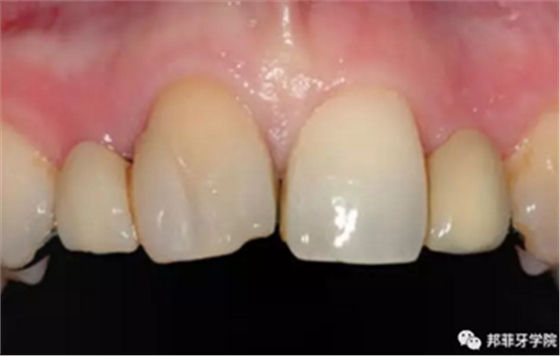

26歲女性患者,雙側上頜側切牙先天缺失,對原有修復體的“形態(tài)”、“光澤”等方面不滿意,希望重新修復(圖1&2)。12及22原為粘接橋修復,11根管治療史;拆除原修復體后余鄰牙完整,未見病理性探診深度。無系統(tǒng)疾病史?;颊咂谕递^高,告知治療流程佩戴臨時卡環(huán)義齒等(圖3)、費用、風險后表示接受治療。

圖1:治療前口內情況